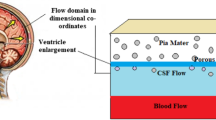

Hydrocephalus is a state in which the circulation of cerebrospinal fluid is disturbed. This fluid, produced within the brain at a constant rate, moves through internal cavities in it (ventricles), then exits through passages so that it may be absorbed by the surrounding membranes (meninges). Failure of fluid to move properly through these passages results in the distention of the passages and the ventricles. Ultimately, this distention causes large displacements and distortion of brain tissue as well as an increase of fluid in the extracellular space of the brain (edema). We use a two-phase model of fluid-saturated material to simulate the steady state of the hydrocephalic brain. Analytic solutions for the displacement of brain tissue and the distribution of edema for the annular regions of an idealized cylindrical geometry and small-strain theory are found. The solutions are used for a large-deformation analysis by superposition of the responses obtained for incrementally increasing loading. The effects of structural and hydraulic differences of white and gray brain matter, and the ependymal lining surrounding the venticles, are examined. The results reproduce the characteristic steady-state distribution of edema seen in hydrocephalus, and are compared with experiment.